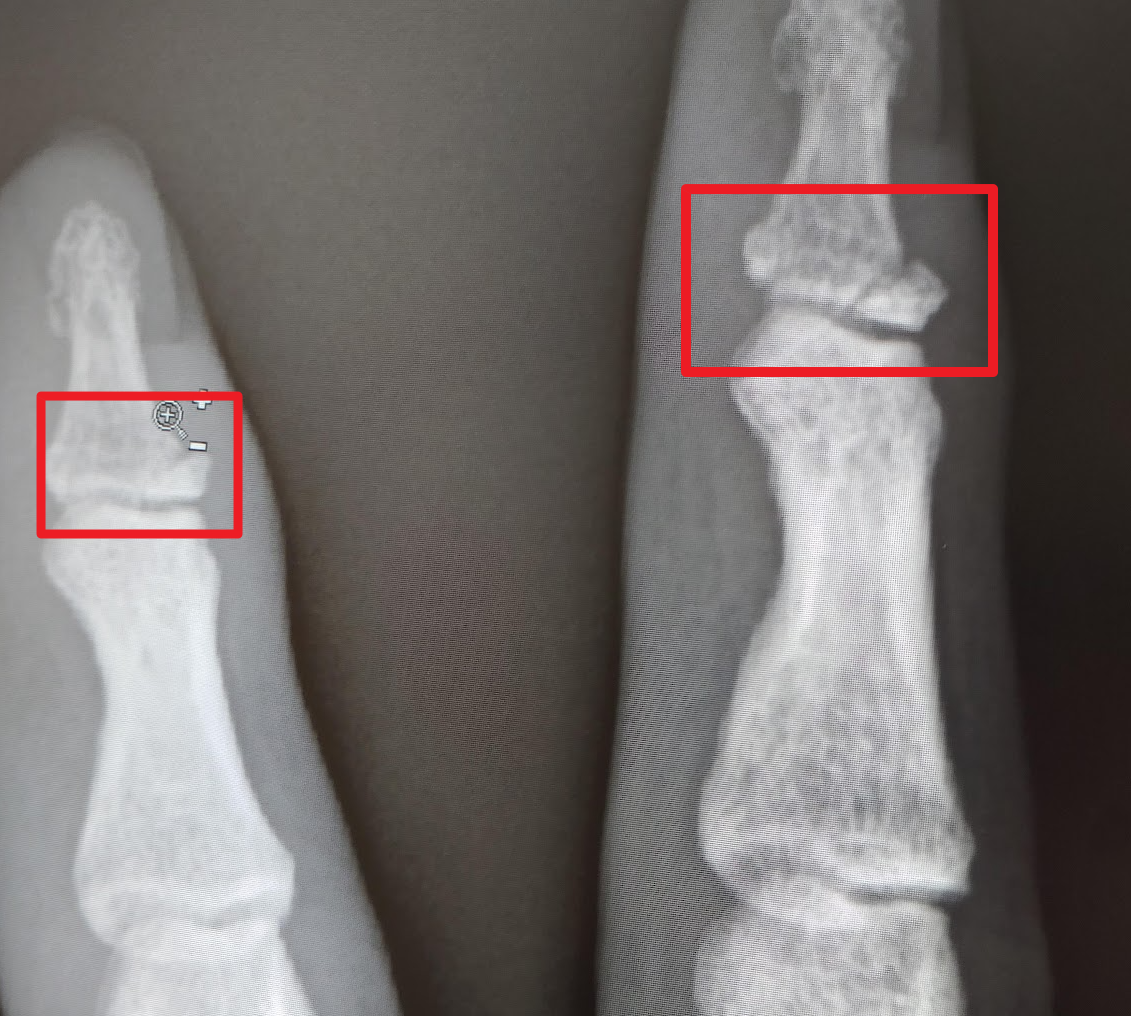

재활을 시작할 때는 의사가 엑스레이 사진을 보고 판단합니다. 대략 6주 차의 X Ray 사진을 보게 되면 뼈가 완전하게 붙지 않았지만 부러진 틈새가 많이 매워져 있는 것을 확인할 수 있습니다. 조금씩 움직여봐도 통증이 많이 줄어들어 어느 정도 회복이 되는 것을 느낄 수 있습니다. 핀을 제거하는 수술을 받는다면 조금 더 회복 기간이 필요합니다. 이때가 되면 재활을 시작해야 한다고 의사가 얘기해주며 일단 조금씩 주먹을 쥐는 듯한 죔죔 형태로 움직이는 것으로 재활을 시작합니다.